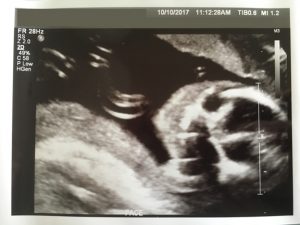

高層次超音波照 – 臉部特寫

我們在的過程中,經由Mrs. A的高層次攝影中看見強健的小寶寶,她一直誇獎寶寶好可愛,真是健康,我相信她在這個職業7年以上經驗的她,應該看過許多不一樣的寶寶,所以也不能不信。每個爸媽都希望小寶寶在媽媽的肚子裡健康成長,不希望有身體的缺陷或是遺傳疾病。最後Mrs. A 列印出臉部特寫及側面臉部輪廓超音波照讓我們帶回家。